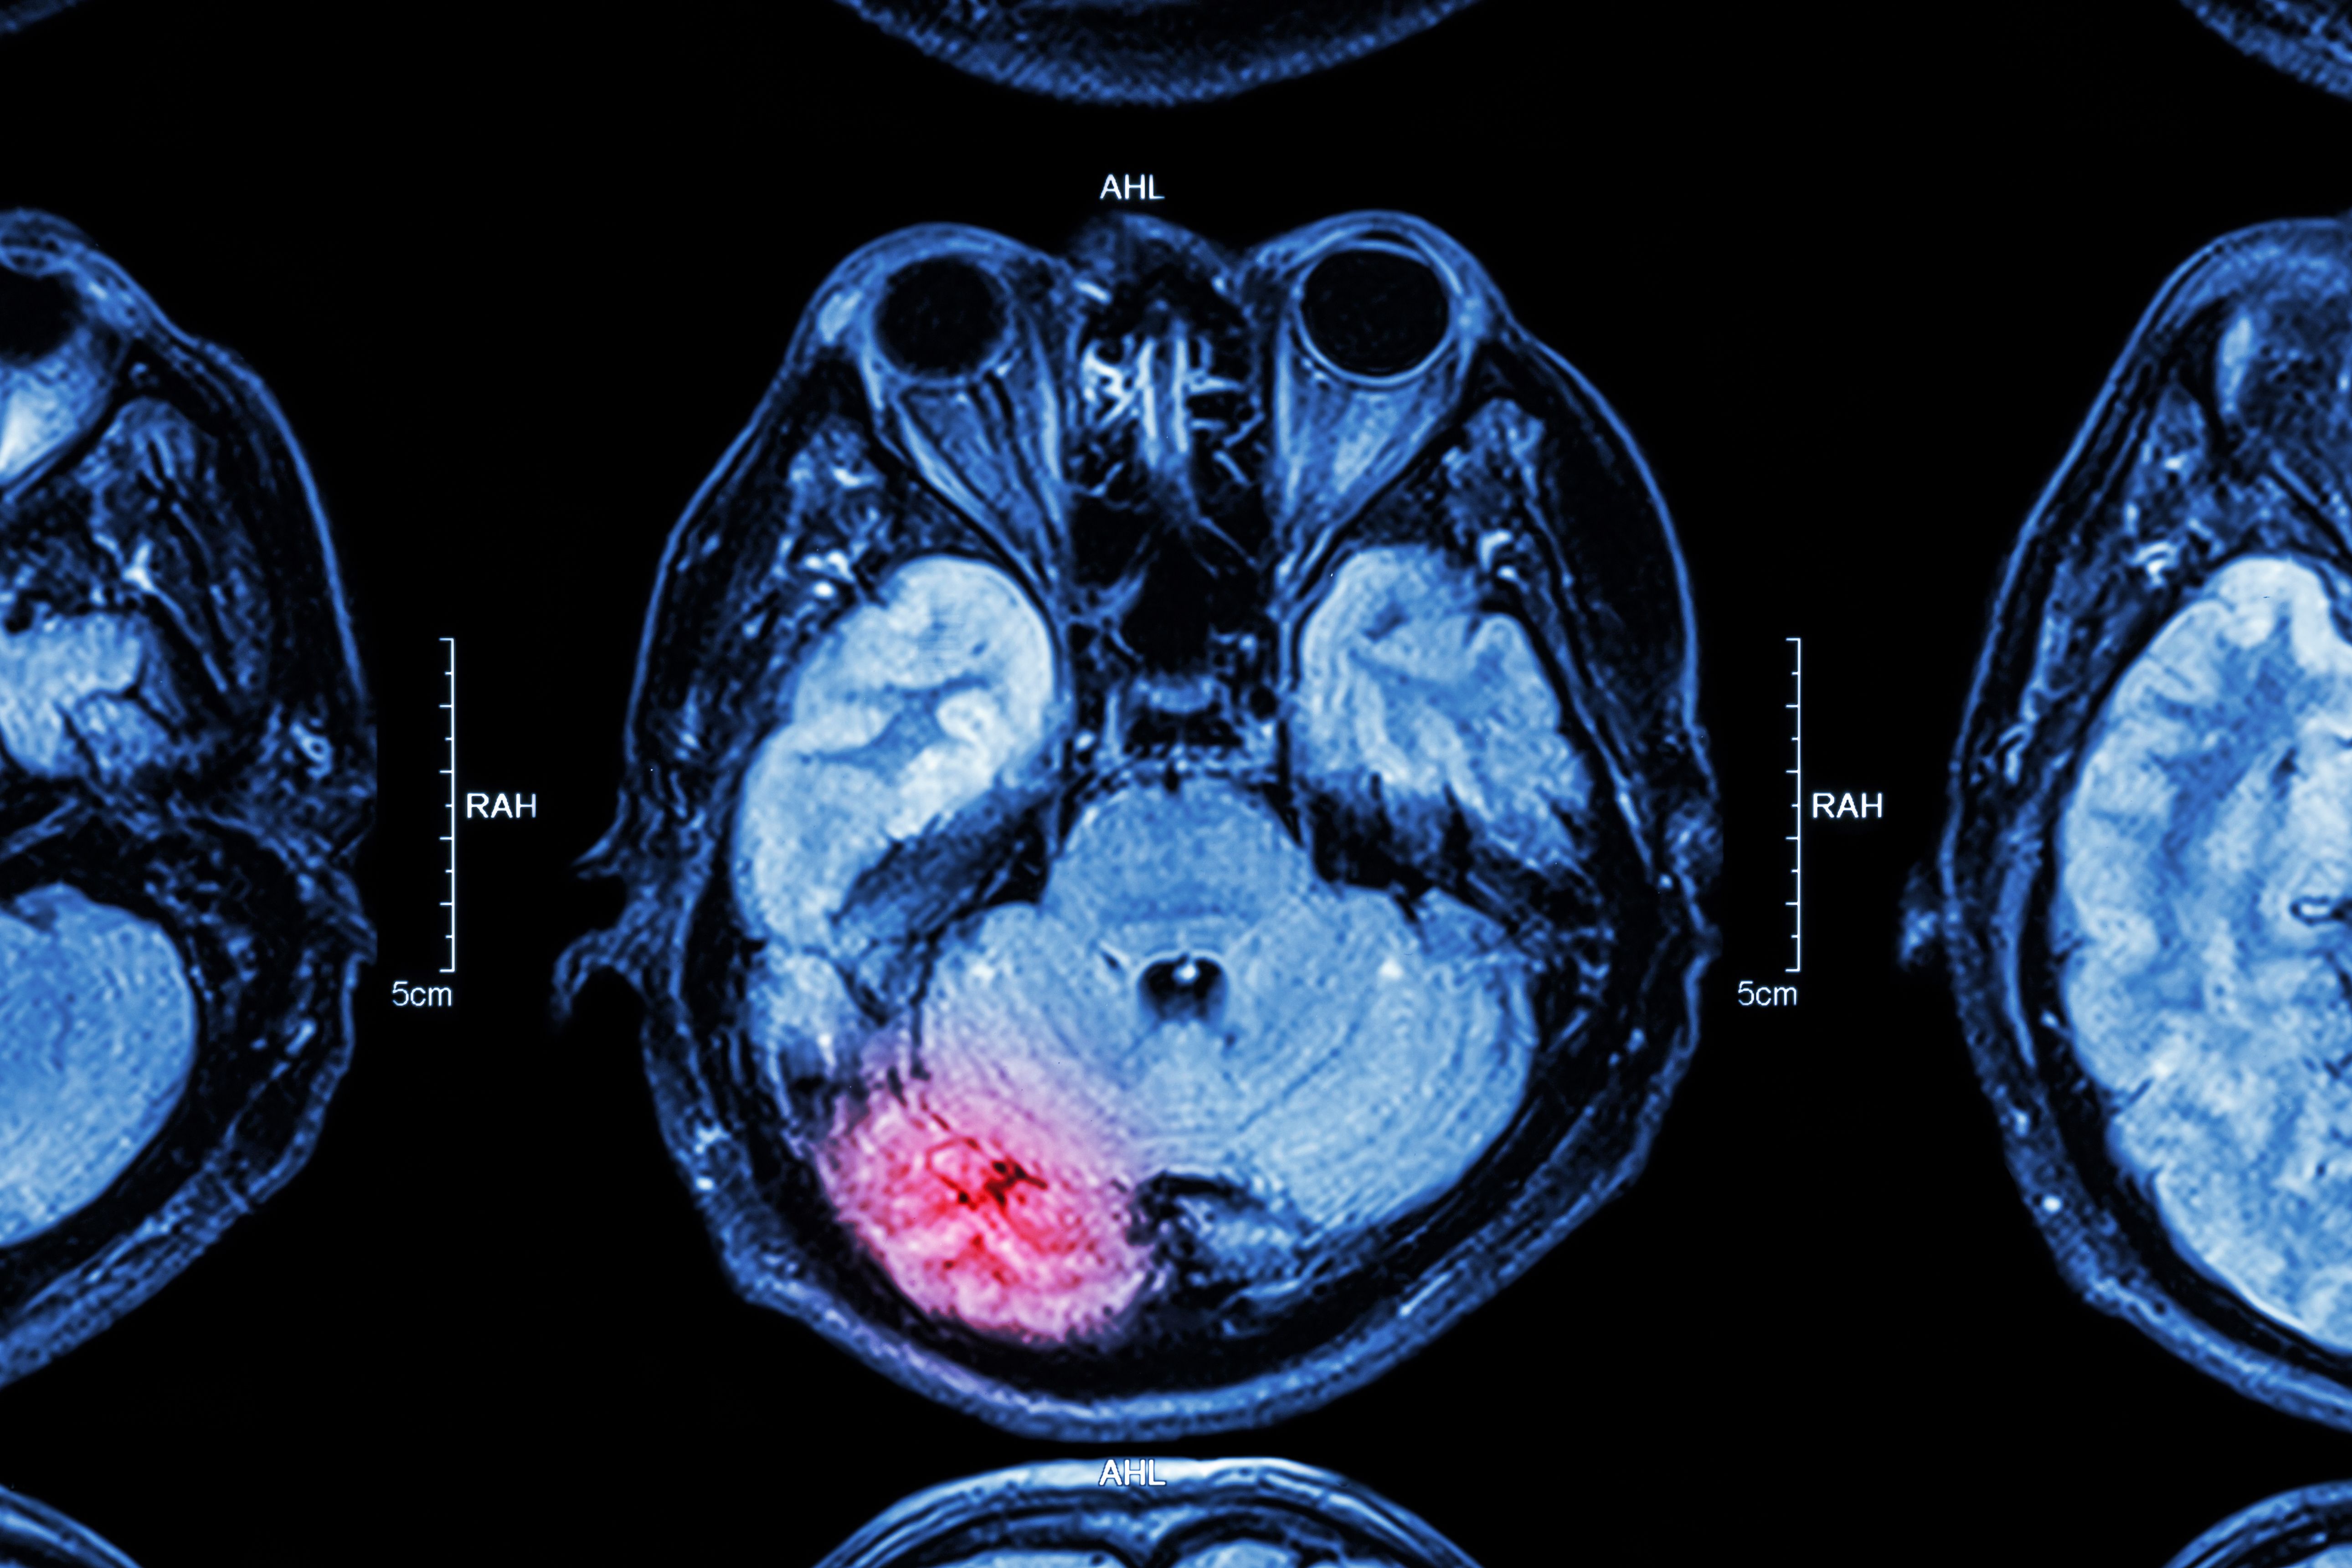

A deep learning algorithm used with brain MRI could help providers identify patients in the early stages of cognitive decline and Alzheimer’s.

Using a model trained on three data sets could lead to automated categorization of “likely normal” and “likely abnormal” brain MRI results.

Announcement opens the 10th annual Brain Tumor Segmentation challenge.